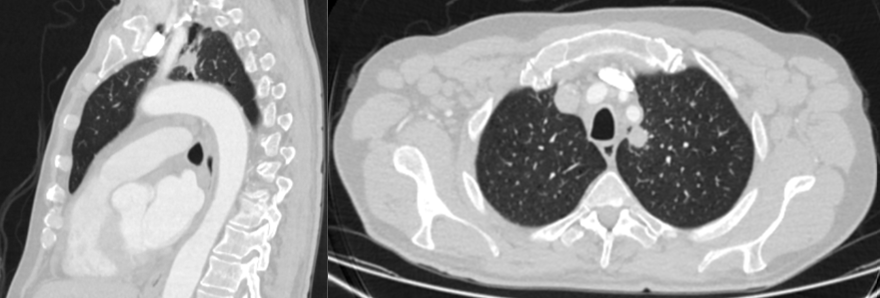

5. Рис. 5. МСКТ органов грудной полости (слева в верхней доле образование солидного типа, с бугристым контуром, размерами 15×14 мм, плотностью +18HU, с градиентом плотности при контрастировании +20+25HU). Примечание: рисунок выполнен авторами | |

6. Рис. 6. МСКТ органов грудной полости (лимфопролиферативный процесс с вовлечением внутригрудных, аксиллярных, шейных, внутрибрюшных и забрюшинных лимфатических узлов, узлов малого таза, гепатоспленомегалия). Примечание: рисунок выполнен авторами | |